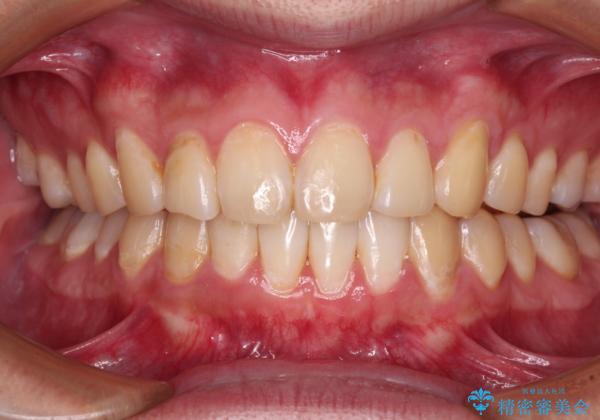

- 上下前歯のデコボコを気にして来院された患者様です。

前歯のデコボコ以外に左側の奥歯の咬み合わせに問題がありましたが、価格を抑え、短期間で気になる前歯を治したいとのことでした。

こちらの患者様は、事前のシミュレーションにより、インビザライン・ライトでは前歯のデコボコを解消しきれないことが分かったため、通常のインビザライン(コンプリヘンシブパッケージ)での治療が必要となりました。

しかし、費用面や期間で悩んでいらっしゃったため、左側臼歯の問題は解決せずに前歯のデコボコのみを改善するシミュレーションを作成し、治療を行うこととしました。

写真より左側臼歯の咬合がタイトではないことが分かりますが、こちらは保定期間に徐々に咬合させていくこととしました。